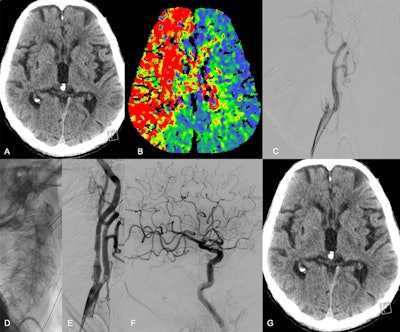

Images in a 74-year-old male patient who presented at the hospital with acute symptoms of a right hemispheric ischemic stroke and a National Institutes of Health Stroke Scale (NIHSS) score of 24. (A) Nonenhanced CT image shows no signs of early infarction, whereas (B) CT perfusion image shows a large perfusion deficit in the territory of the middle cerebral artery and anterior cerebral artery caused by an extracranial occlusion in the right internal carotid artery. (C) Digital subtraction angiography shows the occlusion in the C1 segment. The extracranial occlusion was passed, reperfused, and subsequently stented (D, E). The final contrast injection did not reveal any intracranial occlusions within the territory of the internal carotid artery (F). At the 24-hour follow-up, there was no infarction on (G) the nonenhanced CT image, and the NIHSS score had decreased to 3 points. Image courtesy of RSNA.